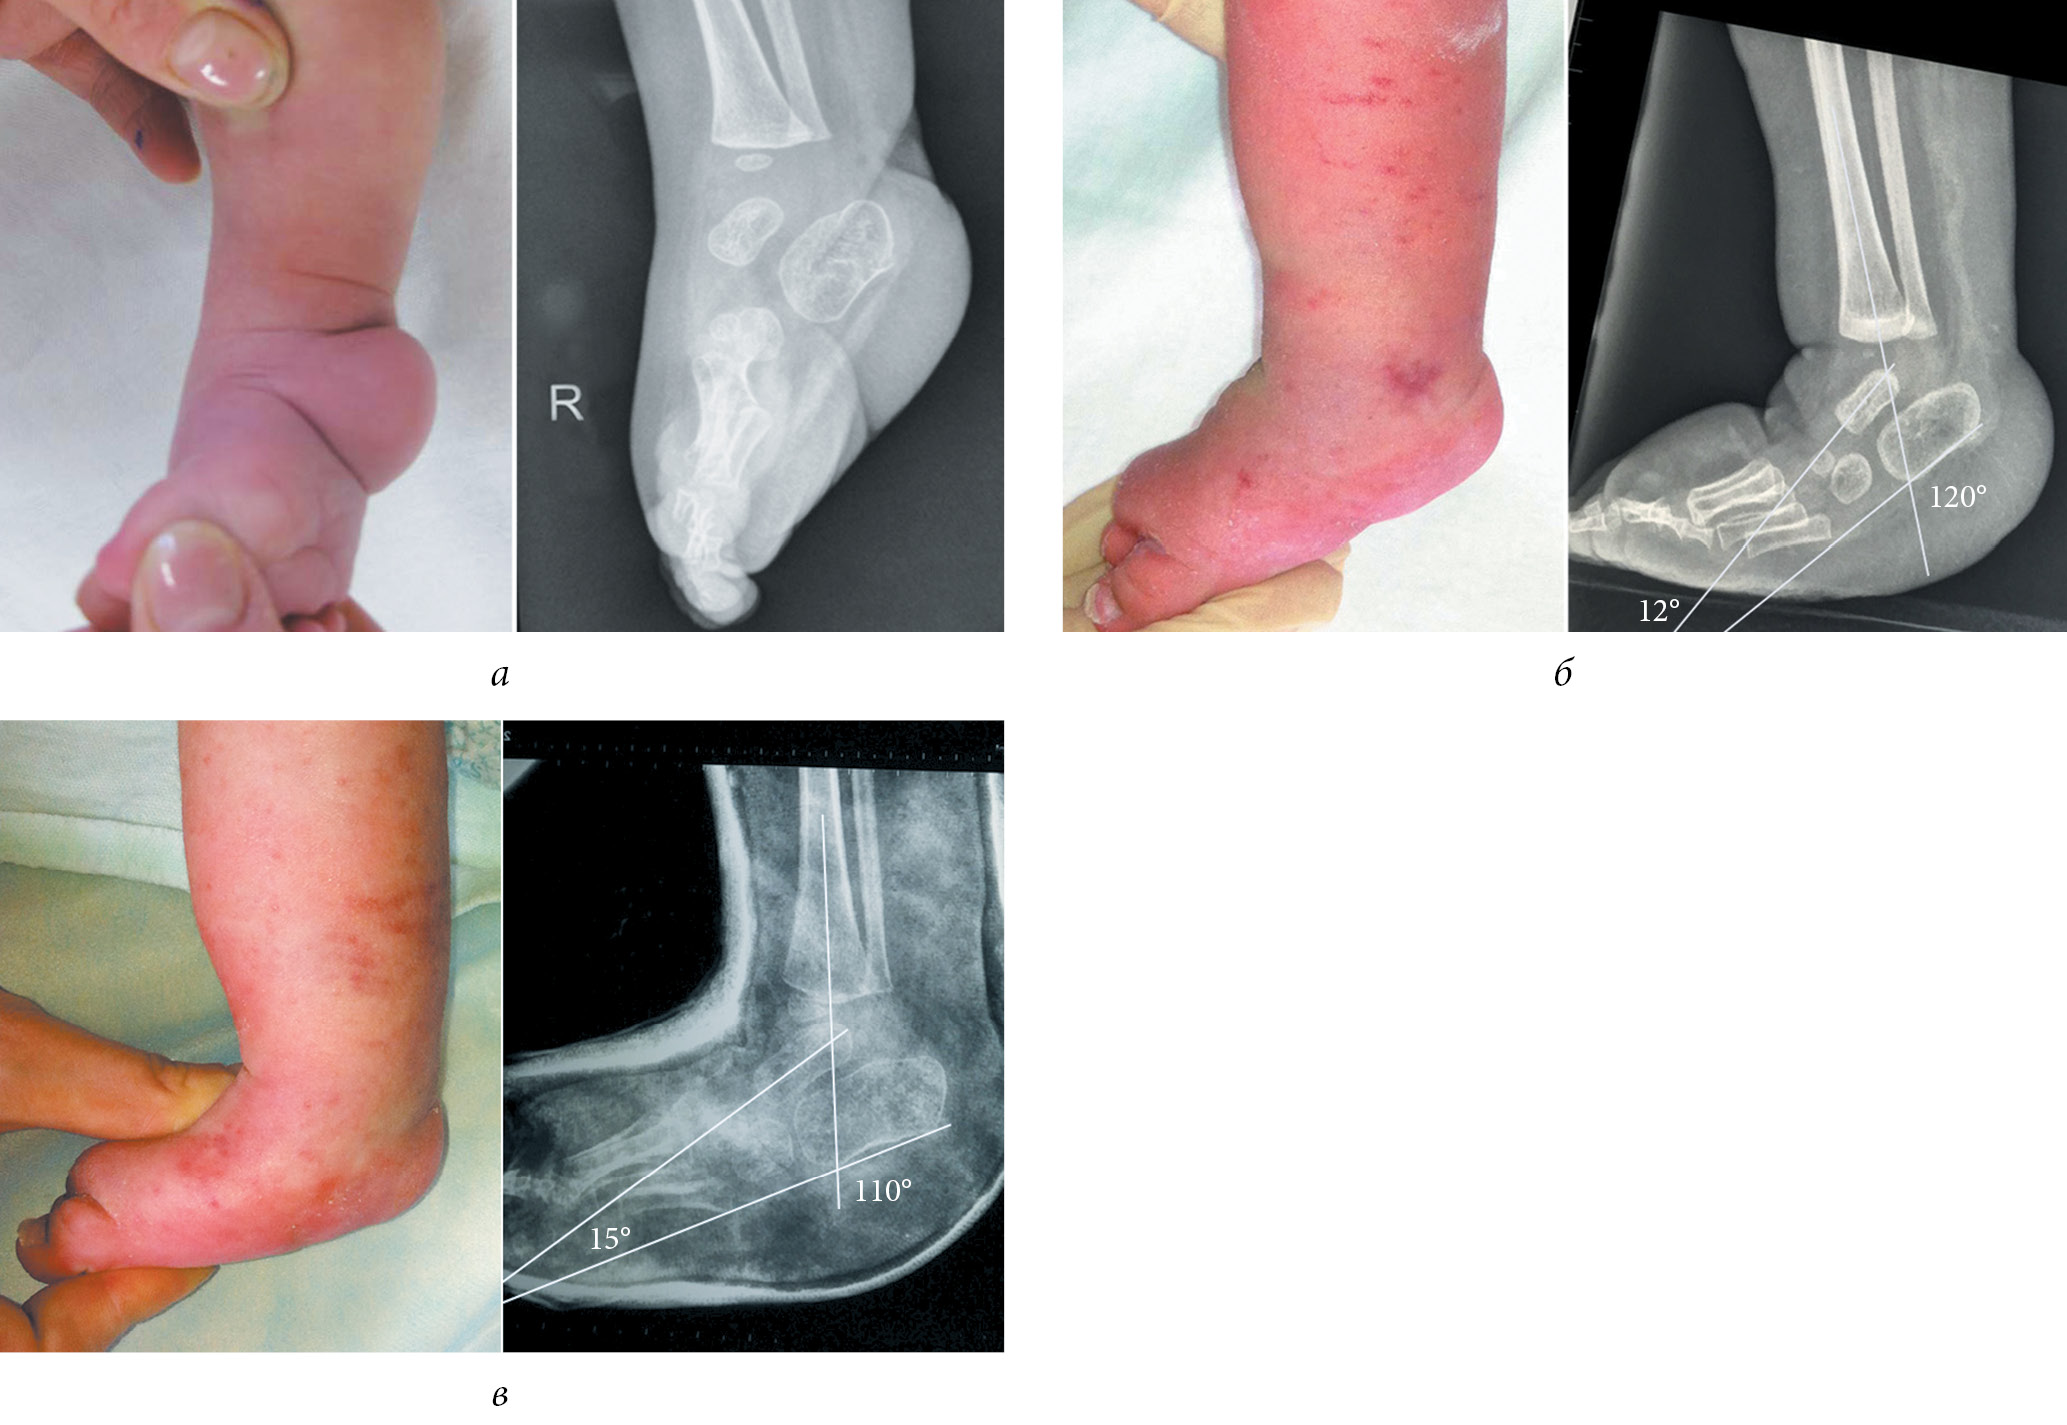

The illustration of some stages of treatment of patients of groups 1 and 2 with clubfoot with arthrogryposis according to the Ponseti method and radiographic data are presented in Figures 2 and 3.

Fig. 2. Appearance and radiograph of the foot in the lateral projection of patient K. with clubfoot with arthrogryposis from group 1: a — before the beginning of casting according to Ponseti; b — before achillotomy; c — after achillotomy; and d — after additional stage casting (two casts)